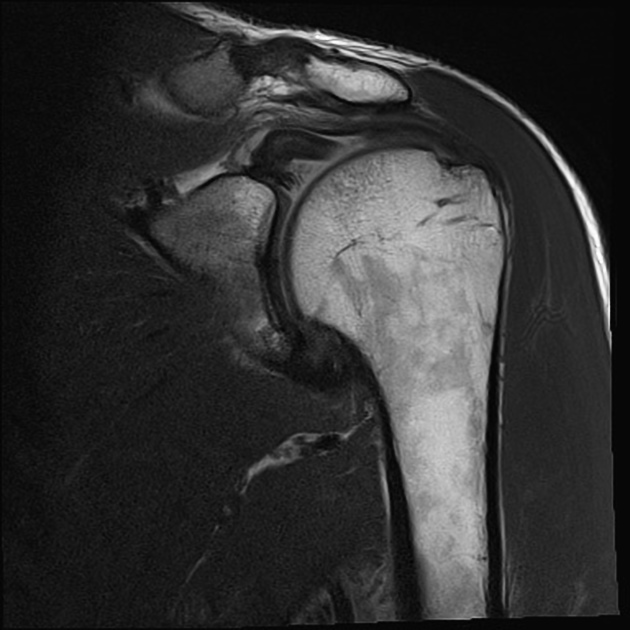

• MRI: Magnetic resonance imaging (MRI) offers detailed images of the soft tissues, including the shoulder and biceps tendons. It helps in assessing the extent of the injury and determining the best course of treatment.